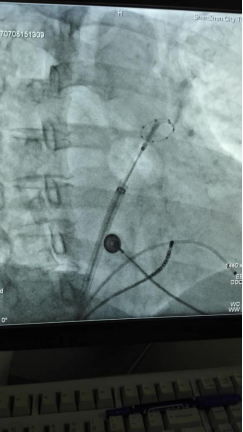

房颤冷冻消融术是一项新技术,其基本原理是利用液态氮气化时带走大量热能,使消融部位温度降低,从而导致组织深度冷冻,使局部组织坏死,从而阻断来自肺静脉的干扰心脏正常跳动的电信号,达到治疗房颤的目的。医生利用冷冻球囊使原先需要数百个点才可能完成的传统射频消融,仅需要数次冷冻消融即可完成对四个肺静脉的电学阻断,大大简化了手术方案。和传统射频消融相比,冷冻球囊房颤消融术更易于医生操作,缩短手术时间,治疗成功率更高,并且减少了血栓形成等严重并发症,术中患者疼痛感明显减轻。